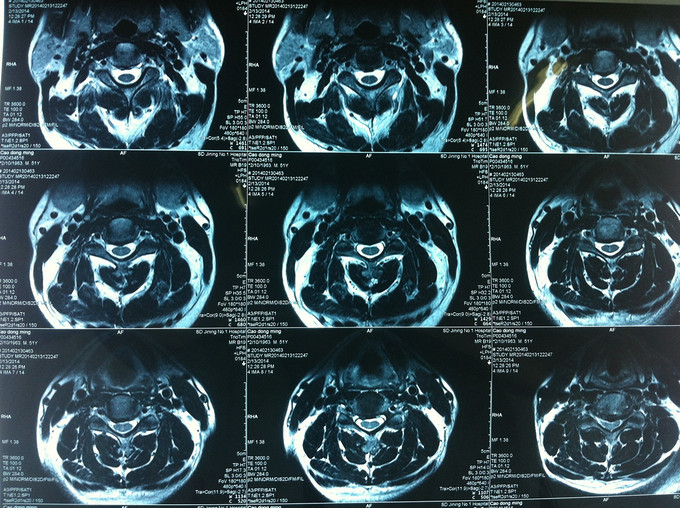

查体:颈后部压痛,颈部活动受限,双侧前臂及手感觉减退,双侧伸腕、伸肘肌肌力4级,双侧霍夫曼综合征阴性,双下肢感觉无减退,双下肢肌张力高,巴氏征可疑阳性,辅助检查: X-ray:劲椎退行性变 CT:颈椎间盘突出,腰5/6 MR:颈椎间盘突出,颈5/6节段明显

诊断:混合型颈椎病 处理: 1、完善相关辅助检查,明确诊断,有无手术指证; 2、完善手术评估,有无手术禁忌,手术风险及并发症; 3、在全麻下行颈椎前路减压,颈5/6椎间Cage植骨融合内固定术